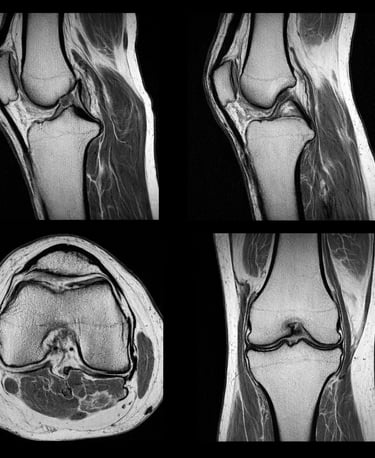

IRM du genou

L’IRM du genou est l’examen de référence pour :

confirmer la lésion

évaluer sa gravité

orienter le traitement

👉 Lire aussi : IRM du genou